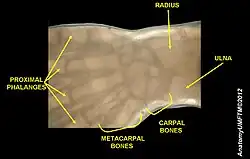

In human anatomy, the wrist is variously defined as (1) the carpus or carpal bones, the complex of eight bones forming the proximal skeletal segment of the hand;[1][2] (2) the wrist joint or radiocarpal joint, the joint between the radius and the carpus[2] and; (3) the anatomical region surrounding the carpus including the distal parts of the bones of the forearm and the proximal parts of the metacarpus or five metacarpal bones and the series of joints between these bones, thus referred to as wrist joints.[3][4] This region also includes the carpal tunnel, the anatomical snuff box, bracelet lines, the flexor retinaculum, and the extensor retinaculum.

Carpal bones of the hand:

- Proximal: A=Scaphoid, B=Lunate, C=Triquetrum, D=Pisiform

- Distal: E=Trapezium, F=Trapezoid, G=Capitate, H=Hamate

In the hand proper a total of 13 bones form part of the wrist: eight carpal bones—scaphoid, lunate, triquetral, pisiform, trapezium, trapezoid, capitate, and hamate— and five metacarpal bones—the first, second, third, fourth, and fifth metacarpal bones.[8]

The earliest carpal bones to ossify are capitate bone and hamate bone in the first six months of an infant life.[9]